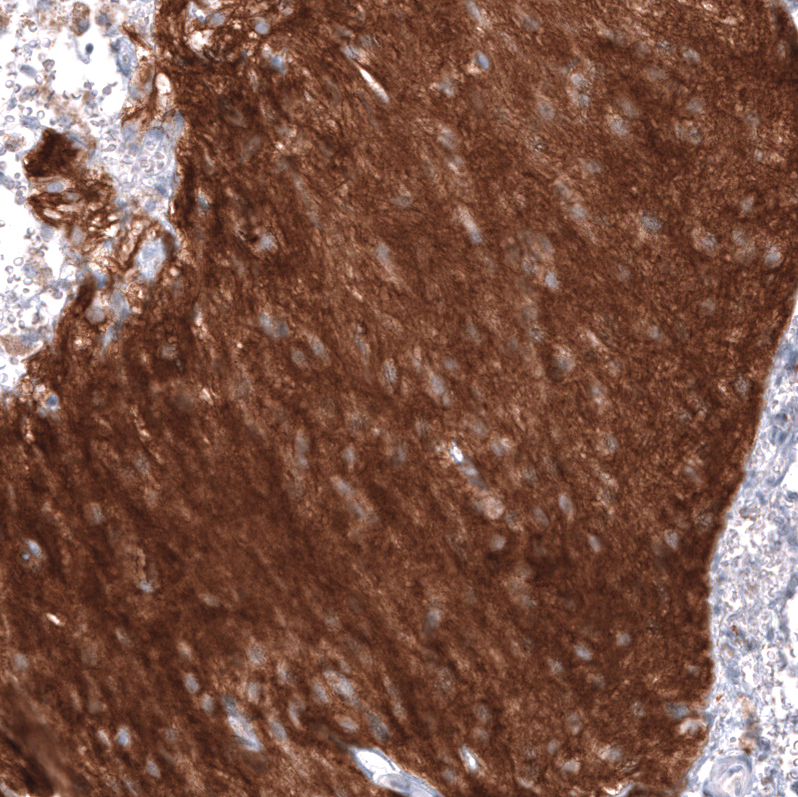

Immunohistochemistry analysis in human cerebral cortex and skeletal muscle tissues using AMAb91807 antibody. Corresponding NCAM1 RNA-seq data are presented for the same tissues.